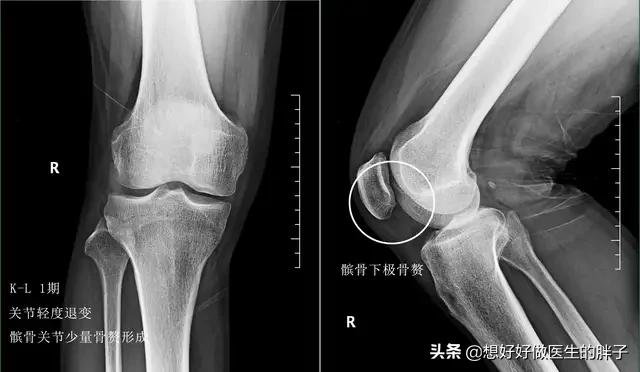

●早期的骨关节炎患者的症状往往不是特别的严重,屈伸活动都不会有很大的影响,有一些患者可能会在上、下楼梯或者是过度劳累的时候出现关节的疼痛,此时去医院进行x线检查,关节间隙一般不会有明显的狭窄,关节内会有少量的骨赘形成,但不是特别大,并不会明显影响患者的功能,往往需要做核磁才能发现关节软骨是否存在着退变。这个阶段需要注意的是控制体重,尽量不要做剧烈的刺激关节的运动,可以做以上的三个基础的康复锻炼就可以了,没有必要训练关节周边的肌肉,因为能进行日常的活动,关节功能的肌肉受影响的程度很轻。这个阶段往往不需要口服特殊的药物,可以口服氨糖三个月的时间观察能否出现症状的缓解。

其实控制骨关节病情的进展在这个阶段往往是最关键的,因为这个时候软骨磨损的情况也比较轻,如果能及时的将其控制住,可以延缓疾病的进展。